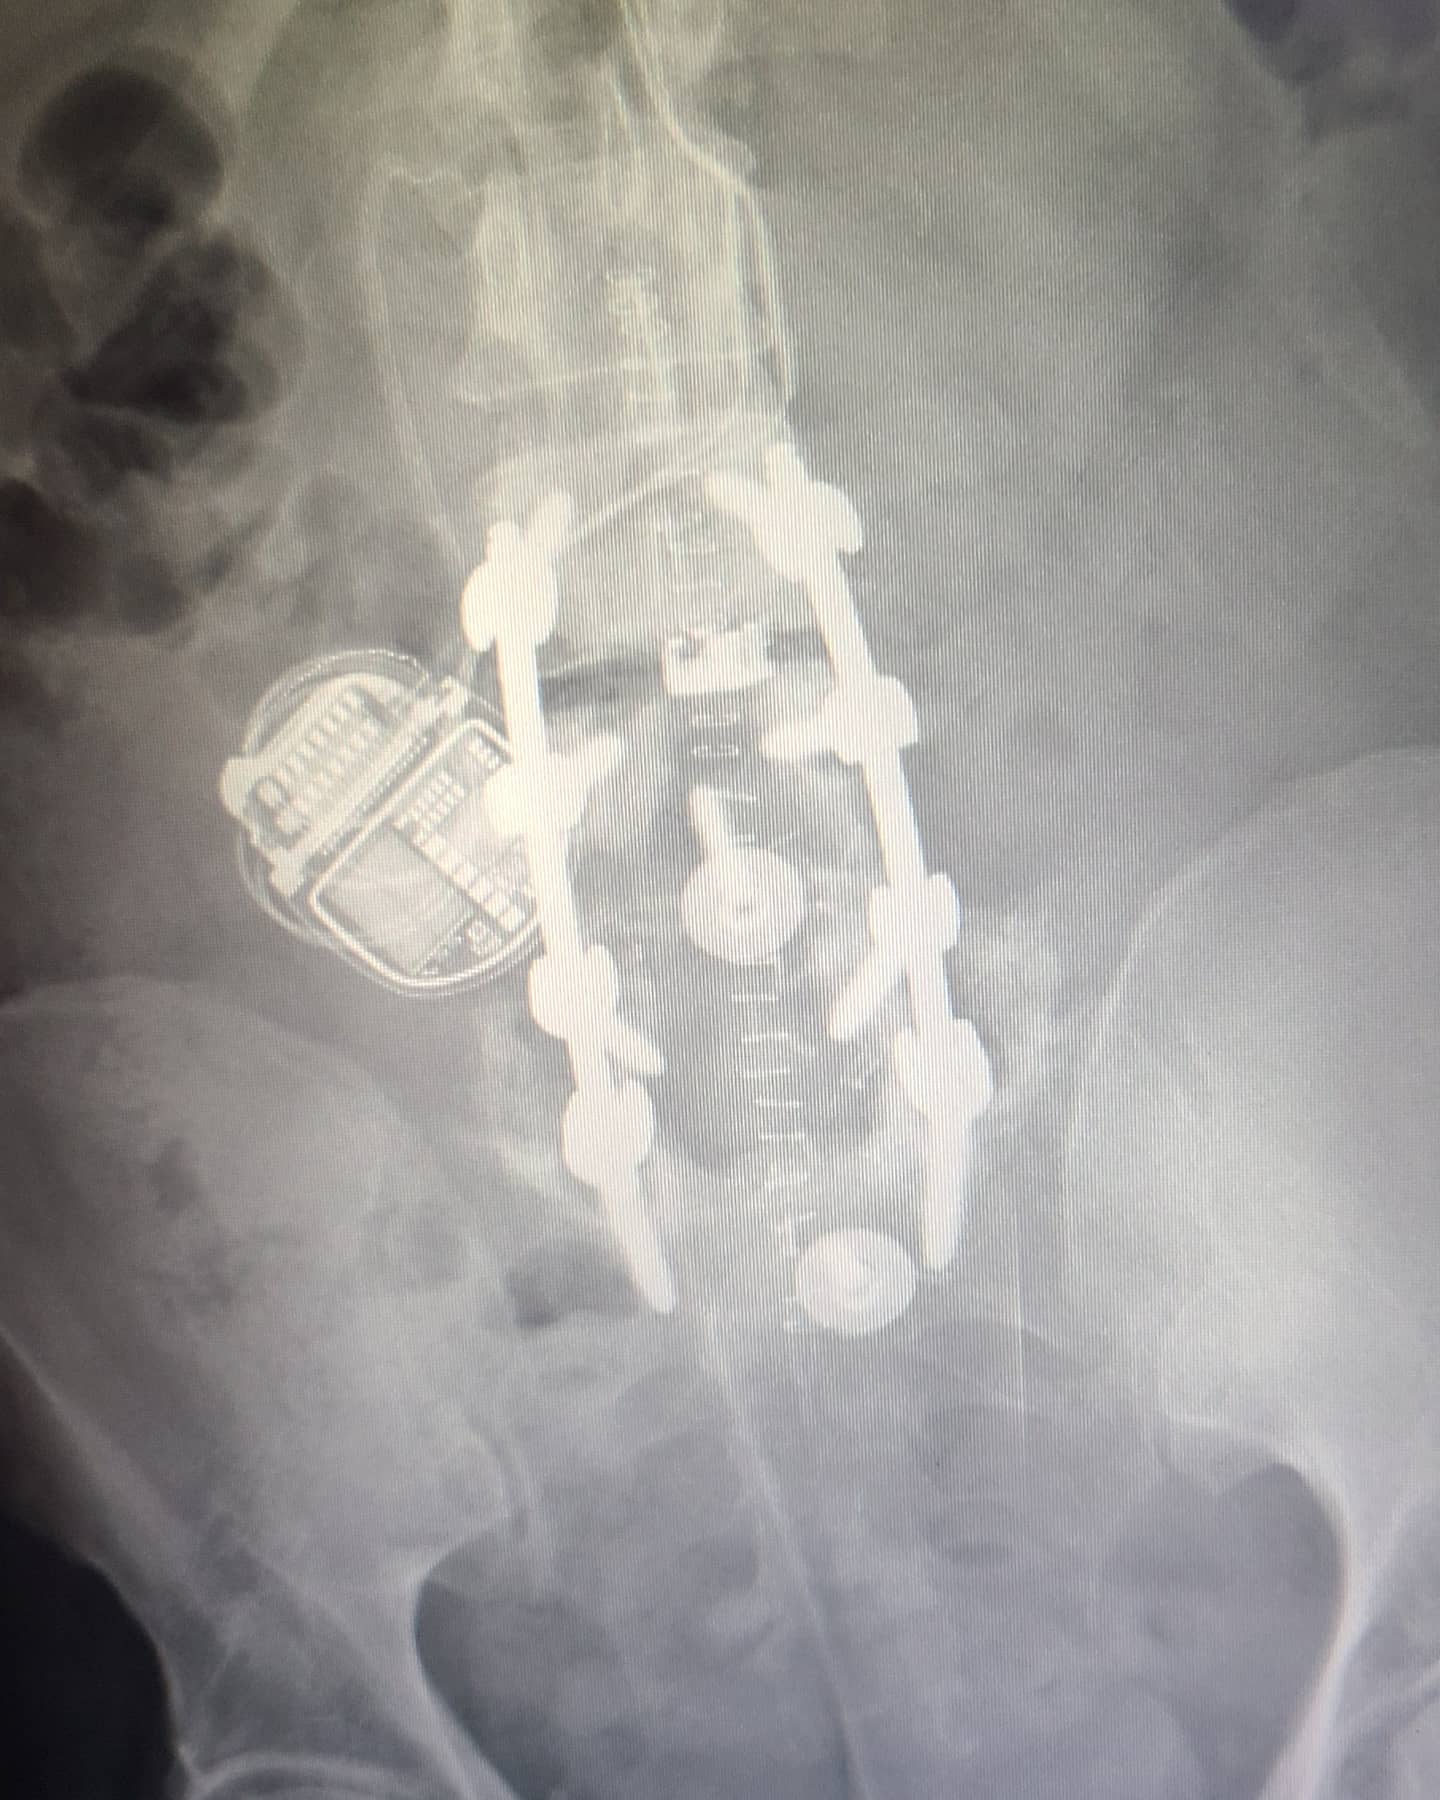

View attachment 7496371

Good Lord dude... that is just hideous. ...and to think I was complaining when they replaced that disc in my neck! :oops: